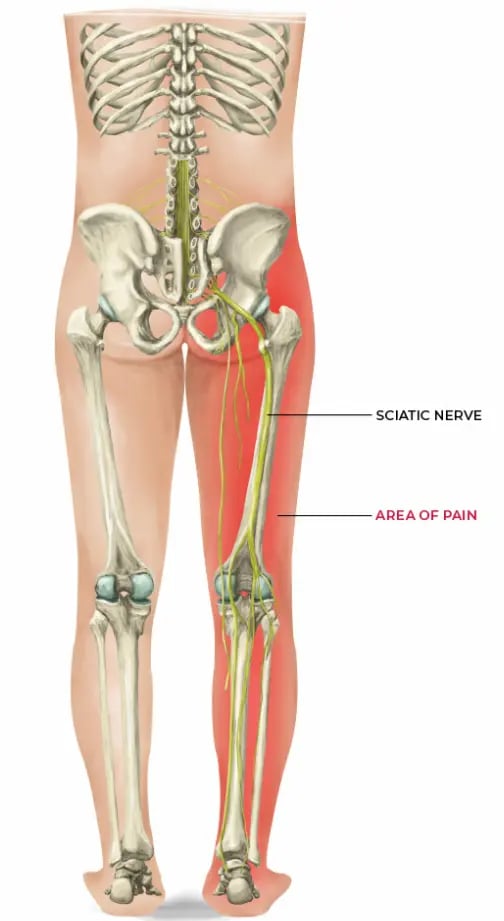

La hernia lumbar puede irritar una raíz nerviosa y provocar:

- Ciática: dolor que baja por glúteo, muslo o pierna

- Hormigueo o adormecimiento en pierna o pie

- Calambres o sensación de corriente

- Pérdida de fuerza (pierna que “falla”, dificultad para caminar de puntillas o talones)

Hernia discal lumbar: síntomas más frecuentes